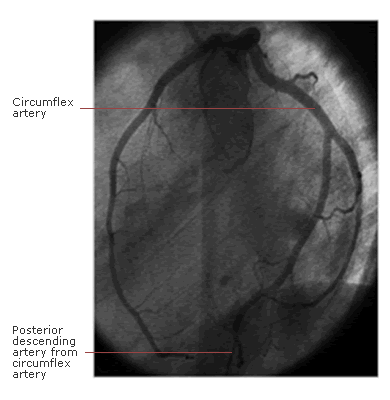

In 15% of people, the posterior descending artery arises from the circumflex artery in the posterior interventricular groove ('left dominance').

Fig 2 shows a labelled, left coronary angiogram